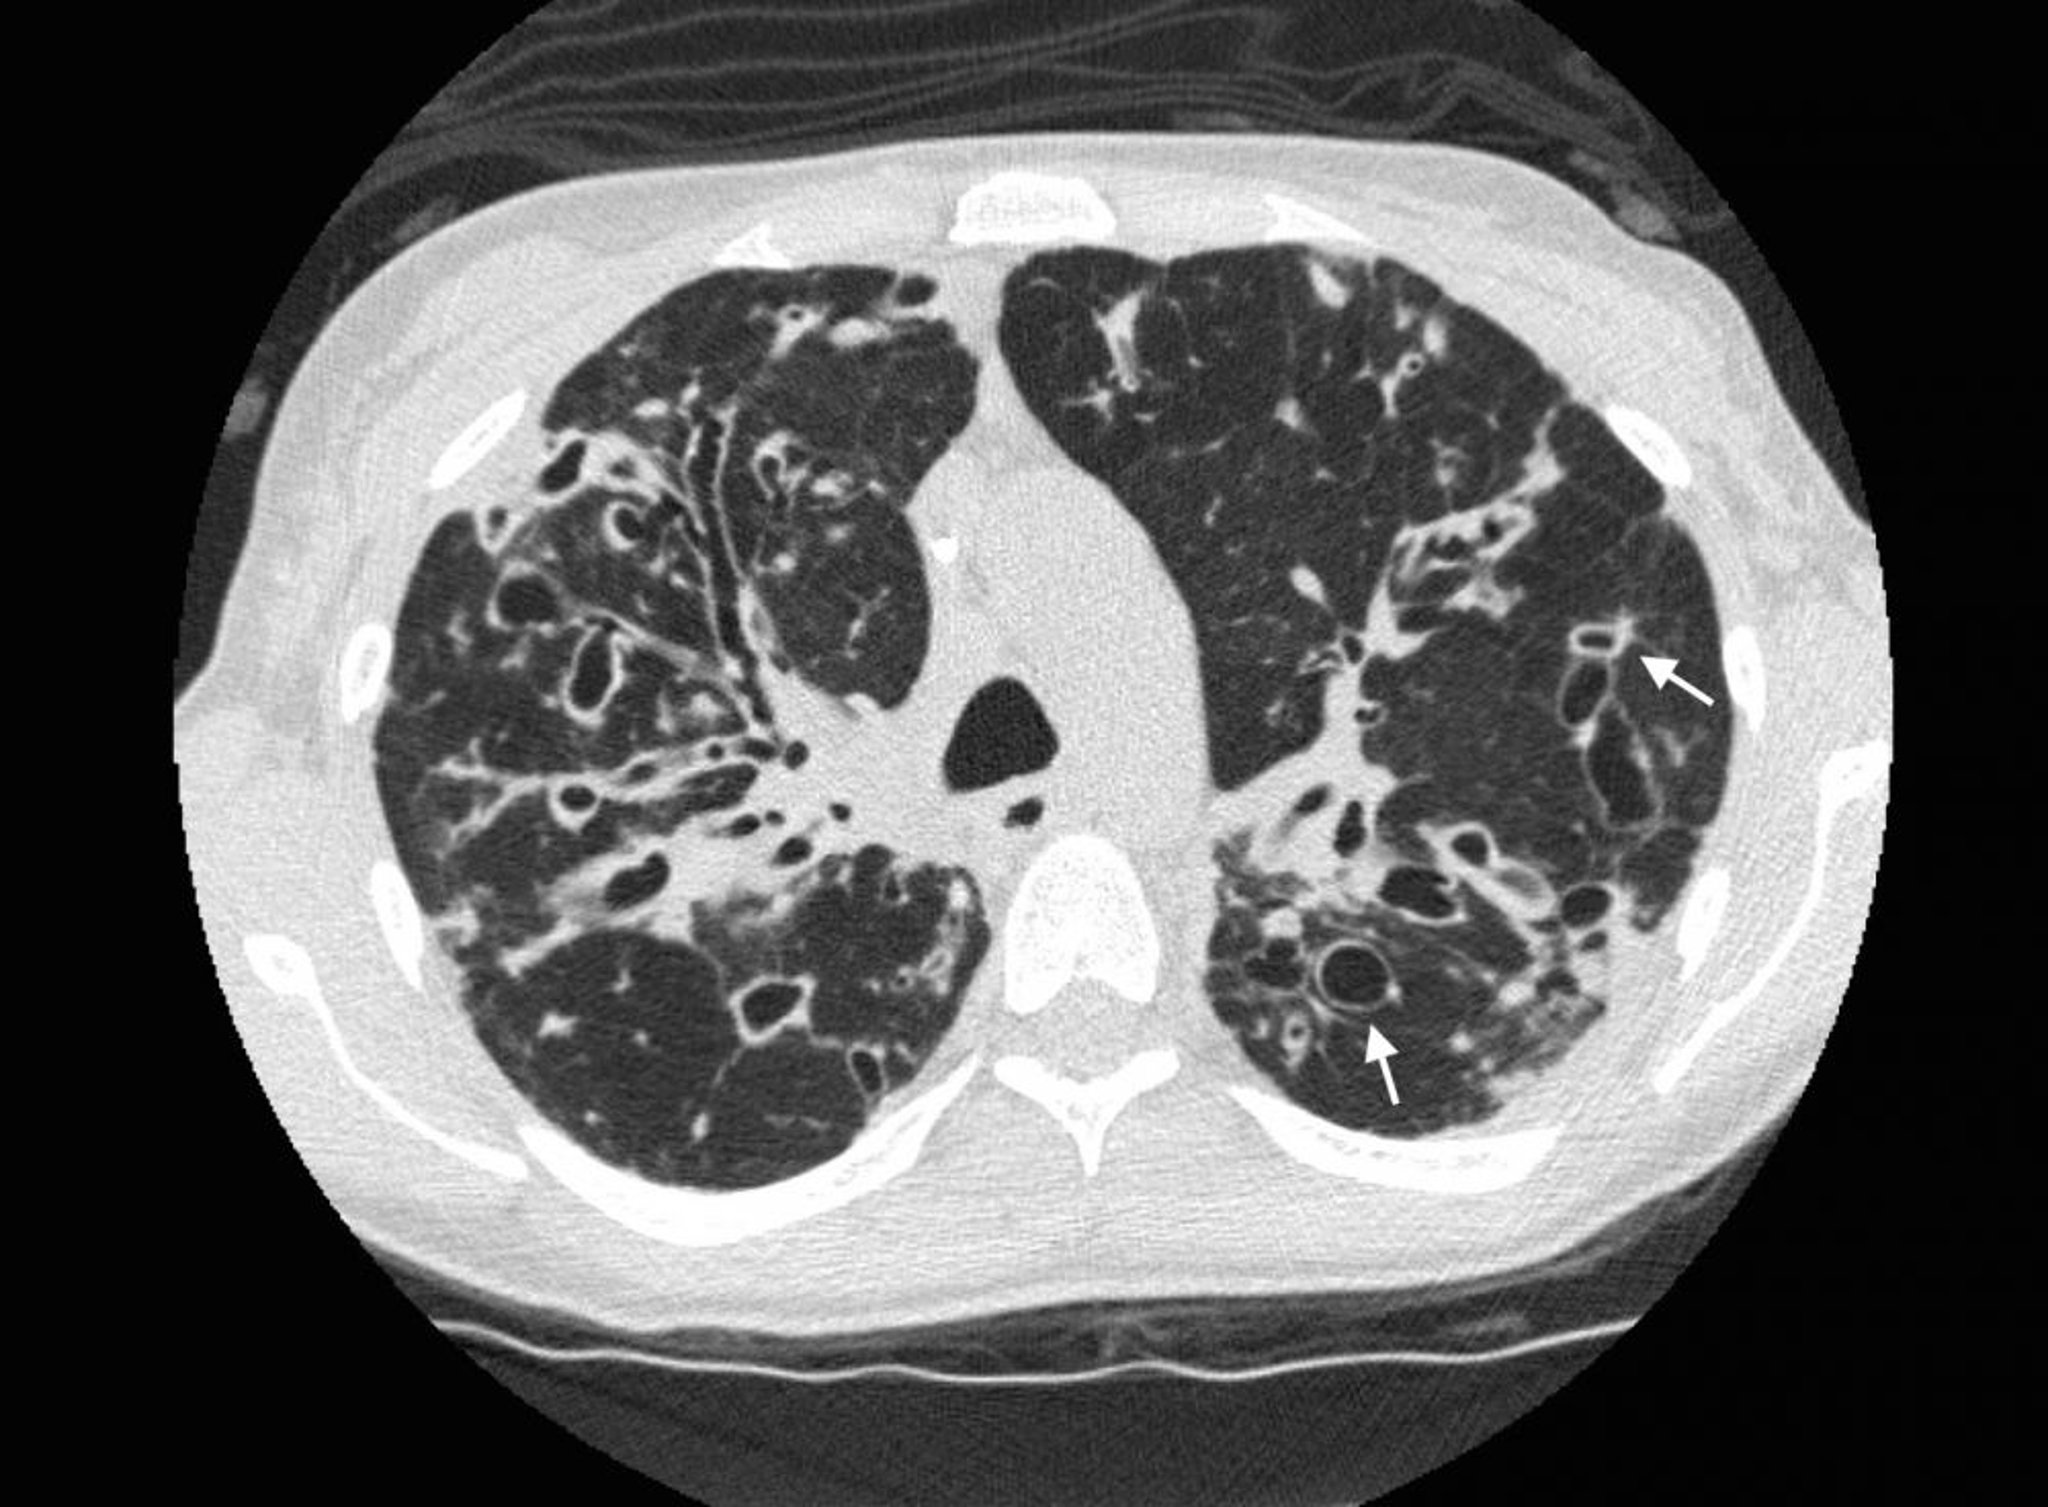

Bronchiectasie (TC)

Una TC del torace in un paziente con fibrosi cistica mostra gravi bronchiectasie nelle zone polmonari superiori con vie aeree dilatate e cambiamenti cistici. Le frecce mostrano il segno dell'anello con castone, in cui una via aerea dilatata (l'anello) è adiacente a un'arteria più piccola (la parte superiore dell'anello). Normalmente, le vie respiratorie hanno le stesse dimensioni o minori delle arterie adiacenti.

Photo courtesy of Başak Çoruh, MD.